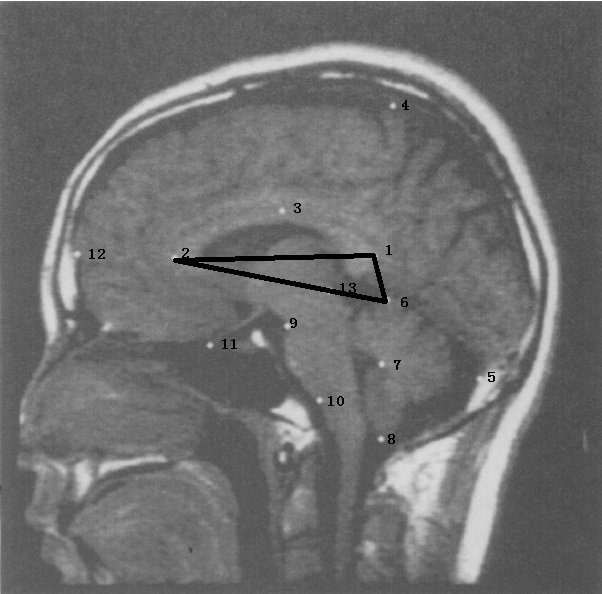

The above three methods provide different viewpoints for our investigation. Method 2 finds a predictor by directly examining the peak values of the parameters (the 2-norm of mean momentum in our case). Method 3 uses Bayesian inference to search for a predictor. By examining the mean momentum, we found an additional abnormal landmark 6 when compared to Procrustes Method. The Bayesian approach, which also models the data, helps to dig out another suspected abnormal landmark 2. The three methods here seem to discover abnormal landmarks at different scales. In Table 5, we summarize the predictors found in the literature and our methods. The results are consistent.

Finally, we comment that from Table 5, the structure differences between the groups of schizophrenia and non-schizophrenia in our database most likely occur at the locations annotated by landmarks 1, 2, 6 and 13. Indeed, the region enclosed by these landmarks (see Figure 9) were investigated in clinical trials and found to be relevant to schizophrenia from some of the literature [21, 31].